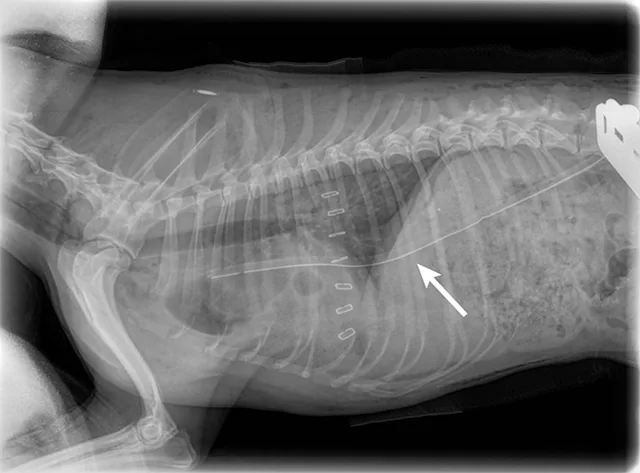

Radiography should be conducted for wounds overlying the thorax or abdomen to look for intracavitary air that may warrant exploratory surgery. Thoracic radiographs should be evaluated for fluid outside the lungs (eg, hemothorax), pneumothorax, and/or rib fractures.3 Abdominal radiographs should be assessed for pneumoperitoneum. Areas between the stomach and diaphragm and ventral to the hypaxial muscles of the spine are common locations for detection of small amounts of air. Free air in the abdomen is a direct indication that emergency surgery is needed.